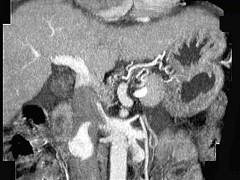

问题 女性,55岁,曾患乙肝,肝硬化多年,右上腹胀痛1月余,CT检查如图所示,最可能的诊断是 ( )

选项 A.肝硬化腹水、下腔静脉血栓形成 B.肝硬化腹水、胆管细胞癌 C.肝硬化腹水、肝癌并下腔静脉癌栓 D.肝硬化腹水、肝脓肿 E.肝硬化腹水、肝血管瘤

答案 C